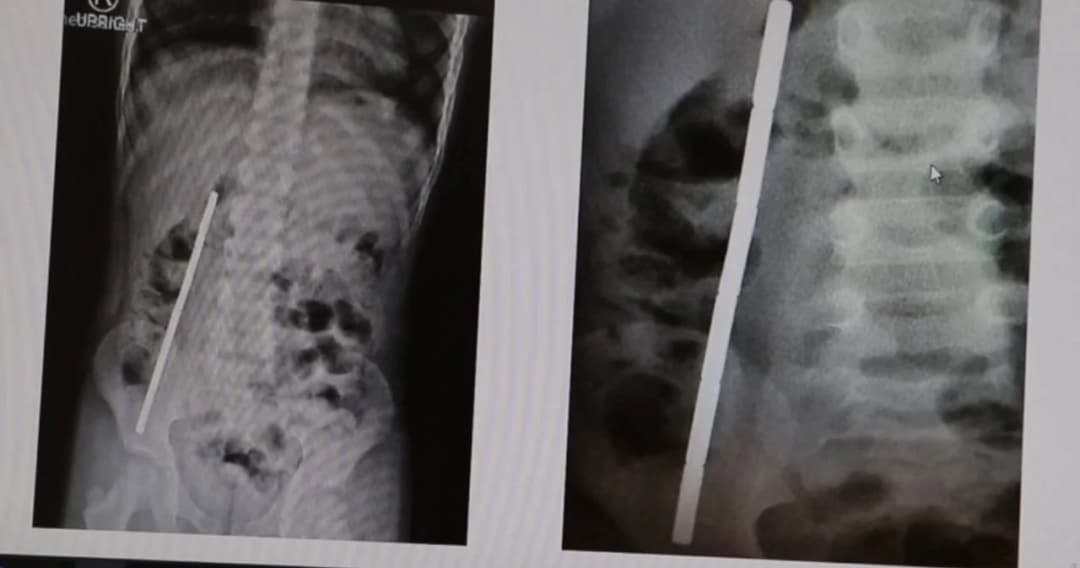

ของเล่น